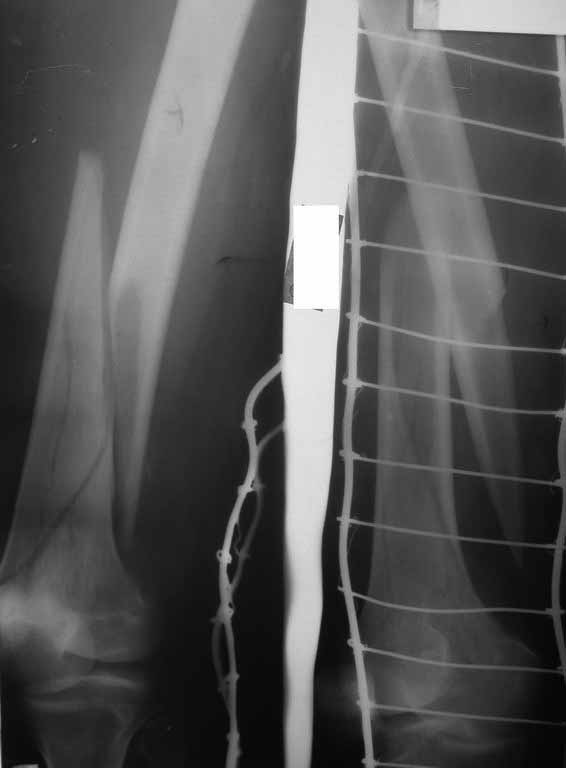

Представляю вам один из наших недавних случаев выполнения малоинвазивного остеосинтеза бедренной кости обычной пластиной 95 градусов. Длина восстановлена с помощью дистрактора (по сути это основная и б(о)льшая часть репозиции). Произведено два небольших доступа, проведена спица направитель. Рентген-контроль для подтверждения достаточной длины/оси (ЭОП использовался в другой операционной). Создание туннеля обратной стороной фиксатора. Поворот фиксатора, введение клинка по спице. Фиксация проксимального и дистального концов пластины.